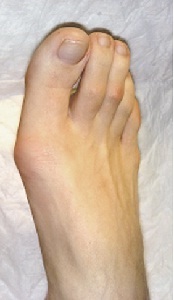

Aspect de oprire (înainte și după 3 săptămâni de chirurgie)

oprire Aspect (saptamana 2-a după intervenția chirurgicală)

Efectul clinic al tratamentului flatfoot (oprire apariție înainte și după intervenția chirurgicală)